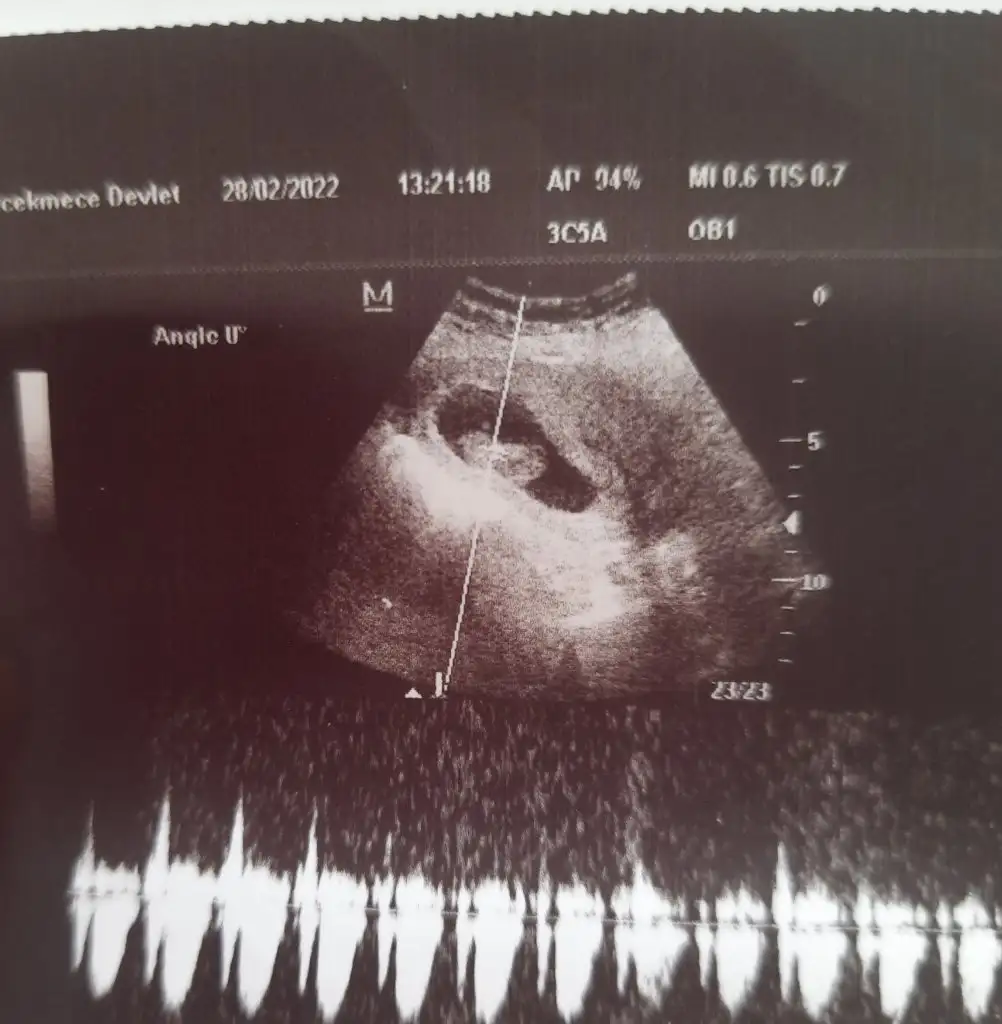

Kızlar sizin usg fotoğraflarında kalp atış hızları yazıyor mu dikkat ettiniz mi?

bi baksana kuzucum sana zahmet, benim 10+3 te 185 çıkmış kalp atışı. 11. Haftadan sonra yavaşlıyormuş 120-160 arasına geliyormuş.Banada hiç demedi ikili testle alakalı birşeydısardayım eve gidince bakayım yazıyormu kalp hızı bn anlamam ama